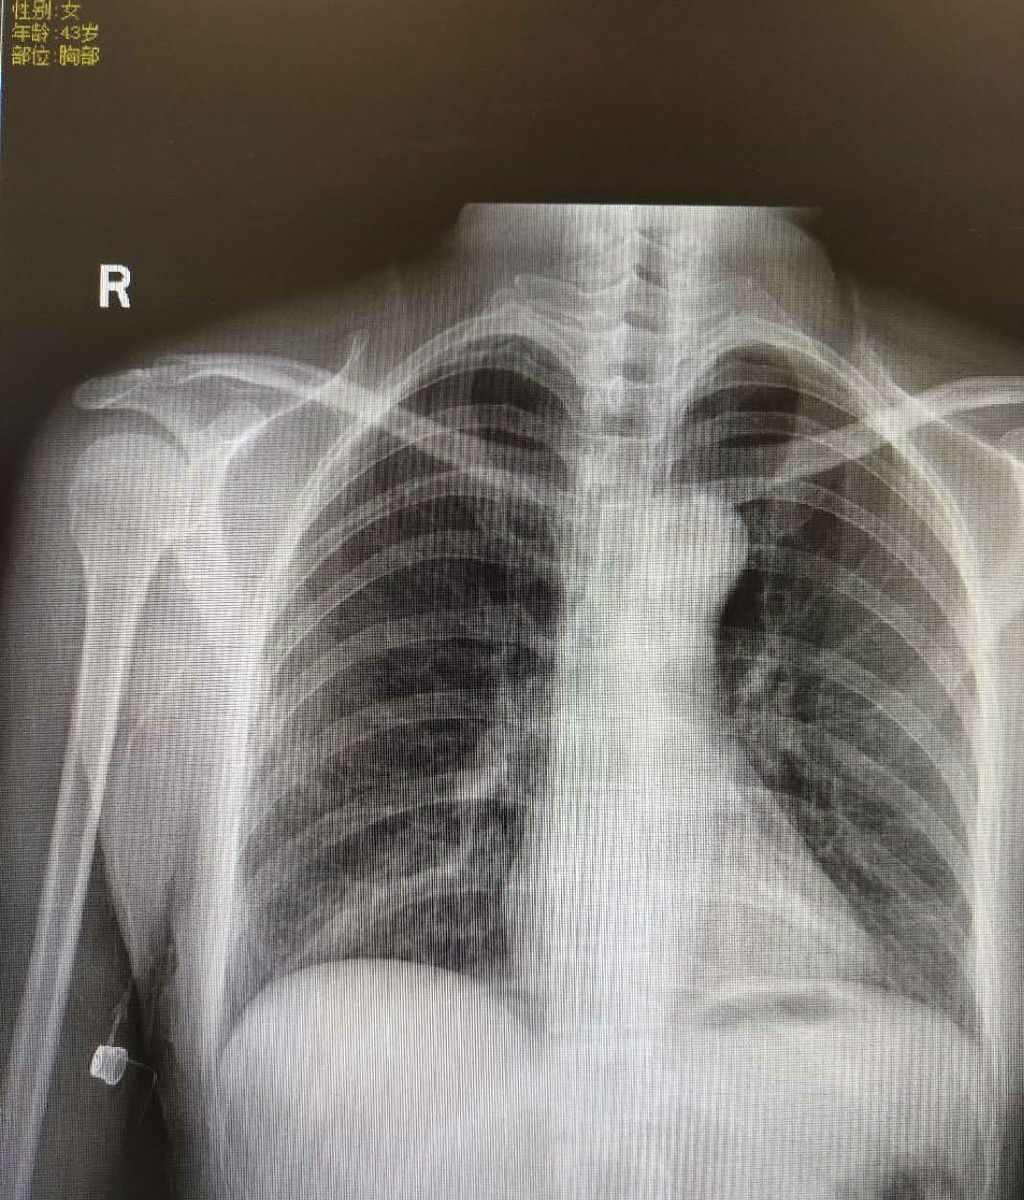

本次手术在超声引导下快速准确穿刺贵要静脉,将心电导联技术应用于导管头端定位,通过观察心电图P波变化确认导管置入长度位于最佳位置;随后在穿刺点下方制作囊袋,建立隧道,连接导管和港座,缝合皮肤,插入无损伤针,病人回病房即可开始静脉输液治疗。全程在无菌条件下,护士置管、医生进行外科操作,团队合作默契,医护配合顺利完成手术。术后患者即可下床活动,胸片检查结果显示导管位置处于理想区间。